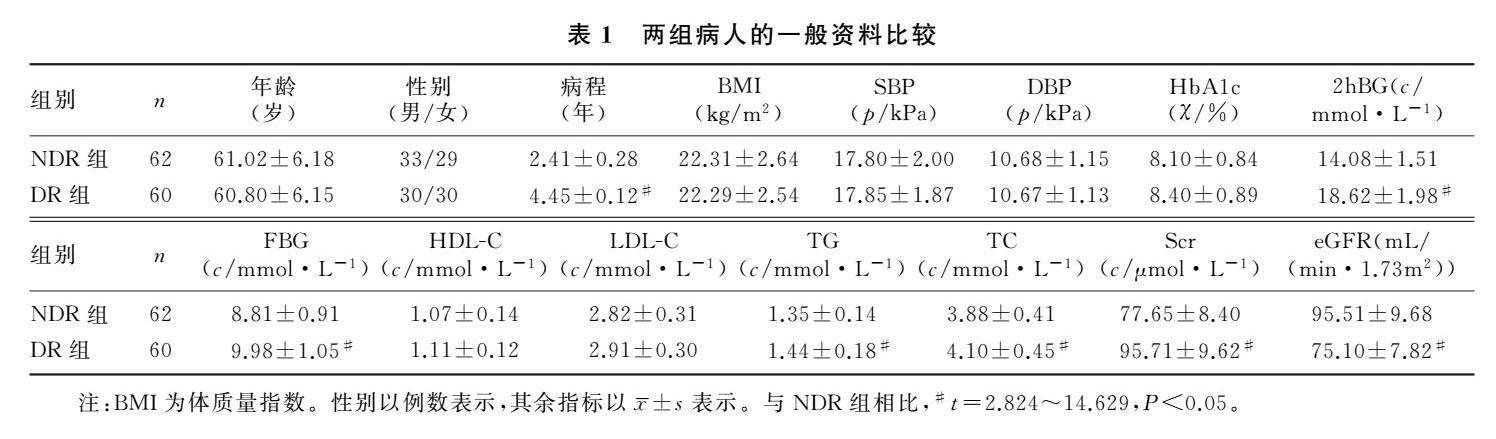

论著 | 糖尿病视网膜病变病人血清STAT1和NQO1水平与视力损伤程度的关系

论著 | 糖尿病视网膜病变病人血清STAT1和NQO1水平与视力损伤程度的关系